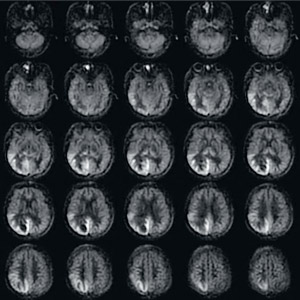

図5 3D ASL(CBFマッピング)による脳膿瘍の画像例

4mm thickness,25slices,5min18s

(画像ご提供:徳島大学様)